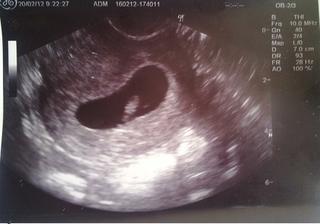

Jsem podle UZ 7+3 (nejsem si teď jistá tím druhým číslem, ale myslím, že tak to paní Dr. říkala 🙂 ) Byla sem pochválena, že zobu kyselinu listovou už od června a na další kontrolu jdu za dva týdny, kdy bude měření mimíska a pak odběry jo a dostanu už i průkajdu 😀 Dr. mi předepsala ještě i listovku, páč ta moje co mám, tak už mi dochází a ještě nějaký vitamíny ...něco z pohanky. A fotečku sem taky dostala, ale musela sem si o ni říct 😀 Tak snad bude i nadále vše v pořádku. A co vy ostatní?

@nettaa juuu juuu no tak fotečku, at to muzu porovnati, zjsitila jsem totiz ze moje lochneska tam ma oproti jinym pekny jezero kolem :D... mne na pozadani uz merila ze ma 12mm :o),.. a o foto jsem si taky musela rict.Jinak mas moc ochotnou doktorku.. super.. tak na tehu jsme temer stejne ja dnes 7tt+4.. ja si mela o tu listovku rict :(.. a ja na nabery az 13.3... tak budes tentokrat mit naskok 🙂

@eliss2 Fotečku sem si nafotila do mobilu, ale zrovna se mi to podařilo všechny fotky vyfocený z února z telefonu při přenosu do PC smazat...sem to šikovná, fakt☹ Vyfotím znova, ale až zítra, ju? Co se týče jezírka, tak musím říct, že tvoje lochneska má fakt větší oproti té mojí 😀 U mě taky něco měřila a podle toho se jí ukázalo kolik tt jsem, ale neuvědomuju si, jestli říkala kolik že to má mm, páč já měla oči přilepený na tu obrazovku a něco sem asi i přeslechla v tom tranzu 😀 Jo a i srdíčko nám "blikalo" 🙂 Moje Dr. je fakt super. Byla sem zároveň i na preventivce. Docela dobře jsme pokecaly a několikrát mi gratulovala k mimi 😀 Já jdu na KO přesně 9.3, takže chvilinku náskok budu mít, ale ne zase tolik 😉 Listovky mi předepsala 3 balení a mám brát 3x denně.